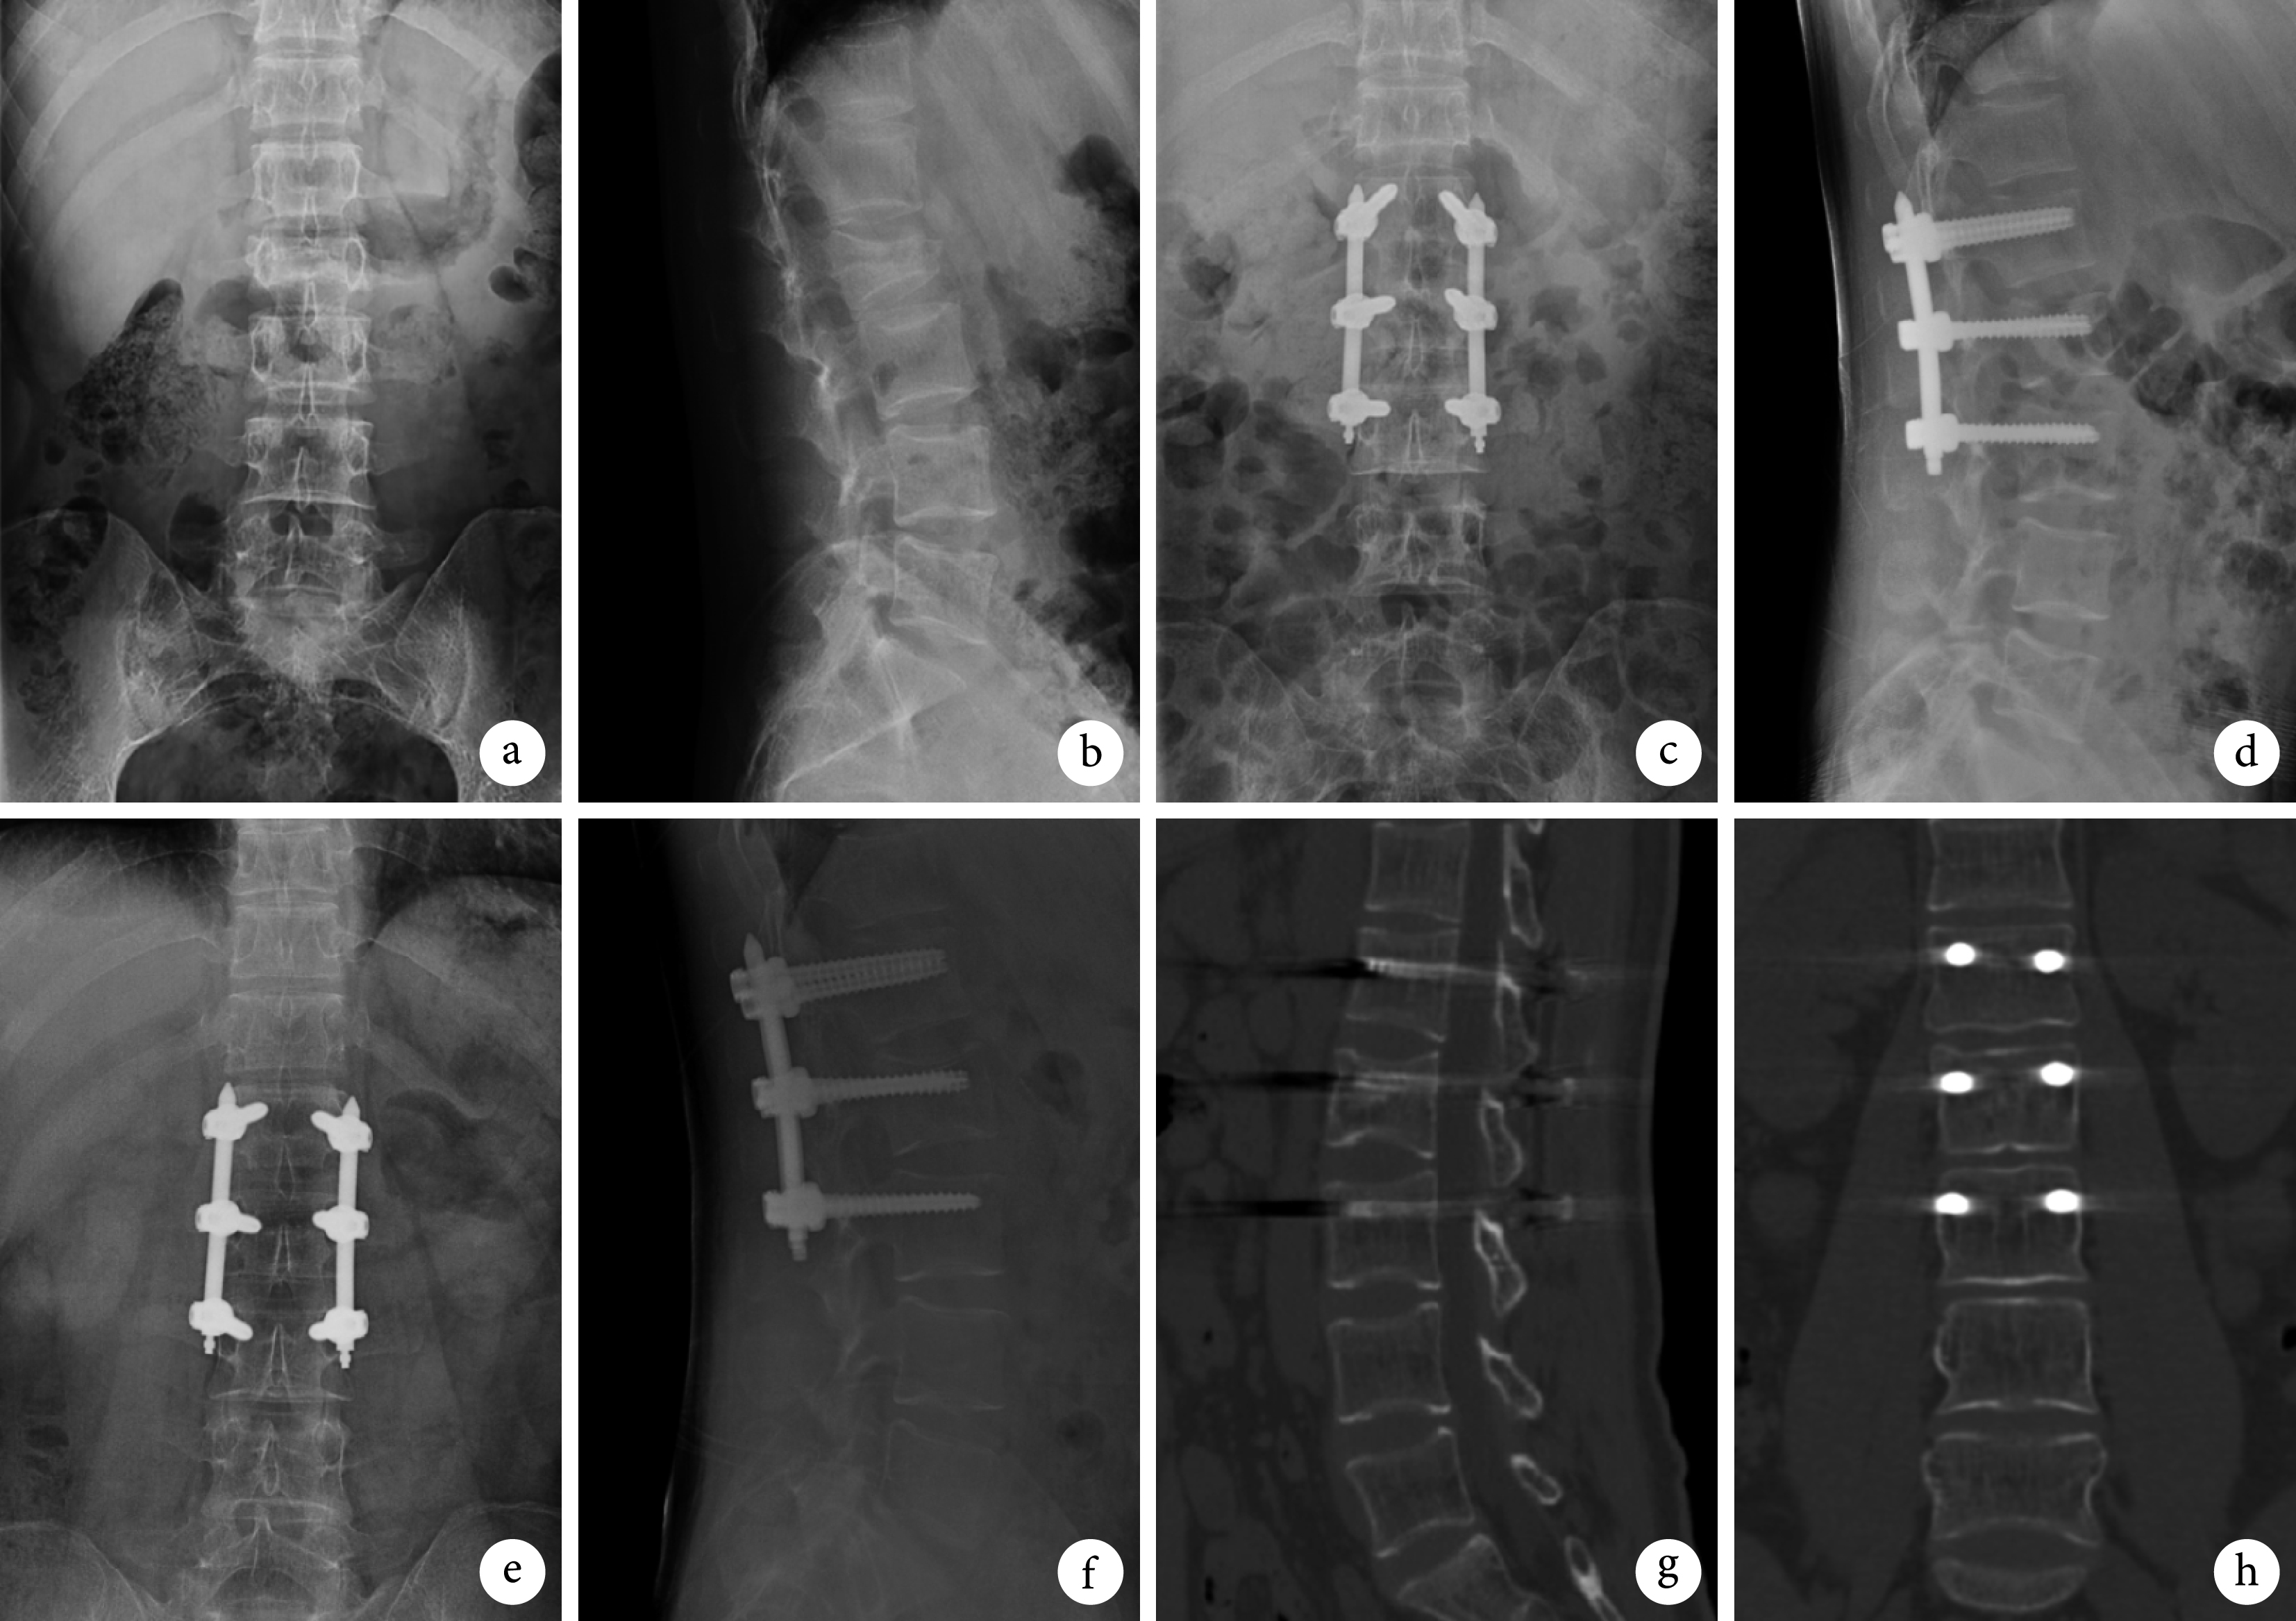

38 例患者均順利完成手術,術中無硬膜囊、神經根、血管損傷等并發癥發生。手術時間(56.2±3.7)min,術中出血量(42.3±3.5)mL。切口無紅腫、滲出,均Ⅰ期愈合。所有患者均獲隨訪,隨訪時間 17~33 個月,平均 21.5 個月。患者腰背部疼痛明顯緩解,術后各時間點 VAS 評分均較術前顯著改善,術后 3 個月和末次隨訪時較術后 1 周進一步改善,差異有統計學意義(P<0.05);術后 3 個月和末次隨訪間比較差異無統計學意義(P>0.05)。隨訪期間無內固定物松動、斷裂及遲發性后凸畸形發生。術后各時間點傷椎前緣高度比和矢狀面 Cobb 角均較術前明顯改善,差異有統計學意義(P<0.05);術后各時間點間比較差異均無統計學意義(P>0.05)。見表 1 及圖 1。

a、b. 術前正側位 X 線片;c、d. 術后 1 周正側位 X 線片;e、f. 術后 18 個月正側位 X 線片;g、h. 術后 18 個月 CT

Figure1. A 32-year-old male patient with vertebral fracture (AO type A3) at L2a, b. Anteroposterior and lateral X-ray films before operation; c, d. Anteroposterior and lateral X-ray films at 1 week after operation; e, f. Anteroposterior and lateral X-ray films at 18 months after operation; g, h. CT at 18 months after operation